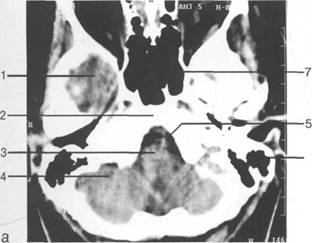

рога боковых желудочков; б - через структуры задней череп 13513u2010n 85;ой ямки.